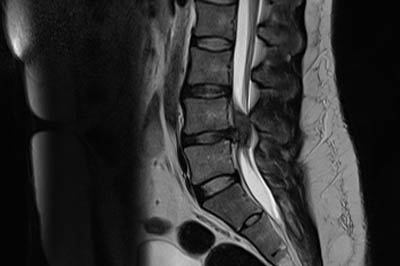

Disc prolapse

disc-prolapse

Disc is a cushion like strecture lying between the vertebral bones.Jelly like substance within the disc is responsible for the flexibility of back bone...

Disc is a cushion like strecture lying between the vertebral bones. Jelly like substance within the disc(Nucleus pulposus) is responsible for the flexibility of back bone. Some times the jelly like substance comes out of its boundary and is called as disc prolapse .

disc-prolapse-intro

Disc prolapse if occurs in the neck it causes neck pain with arm pain. If it occurs in low back it causes lowback pain with leg pain.Pt might also have weakness and numbness of arm or leg depending upon the severity of nerve compression.

Xray is the first investigation needed. MRI may be needed if pain or weakness is severe.

Mostly pain will subside with physiotherapy , rest and pain medications. Discectomy surgery might be needed if pt has persistent arm or leg .